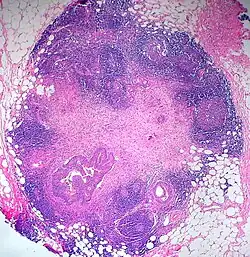

Zunehmend gibt es Tumoren (z. B. Mammakarzinom), bei denen es als ausreichend angesehen wird, nur den sogenannten Wächterlymphknoten (Sentinel Lymph Node) zu untersuchen. Das ist der erste Lymphknoten (manchmal auch mehr als einer), der die Lymphe aus dem Gebiet des Tumors aufnimmt. Finden sich in ihm keine Metastasen, so ist die Wahrscheinlichkeit, in den „nachgeschalteten“ Lymphknoten Metastasen zu finden, sehr gering. Umgekehrt müssen die nachgeschalteten Lymphknoten genau untersucht werden, wenn der Wächterlymphknoten befallen ist. Wurde dieses Verfahren angewendet, wird die pN-Kategorie durch (sn) gekennzeichnet, also z. B. pN0(sn) = histologisch keine Lymphknotenmetastasen, pN1(sn) = Befall des (der) Wächterlymphknoten.